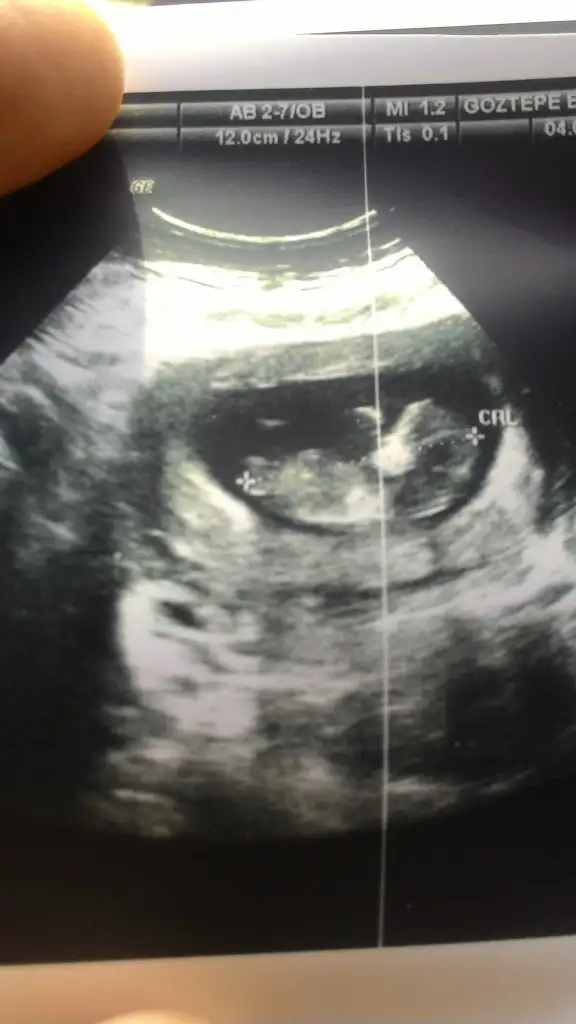

dr soylemeden siz gorun genital nub teorisi ( bebegin cinsiyeti)

Kizlaar tahminlerinizi alabilirmiyim anlayan herkesten yorum bekliyorum. Ben hic anlamam ama burdaki görüntülere gore yorum yaptım bakalım sizde ayni fikirdemisiniz

Kaç haftalık sanki erkek gibi başka usg de paylaşın